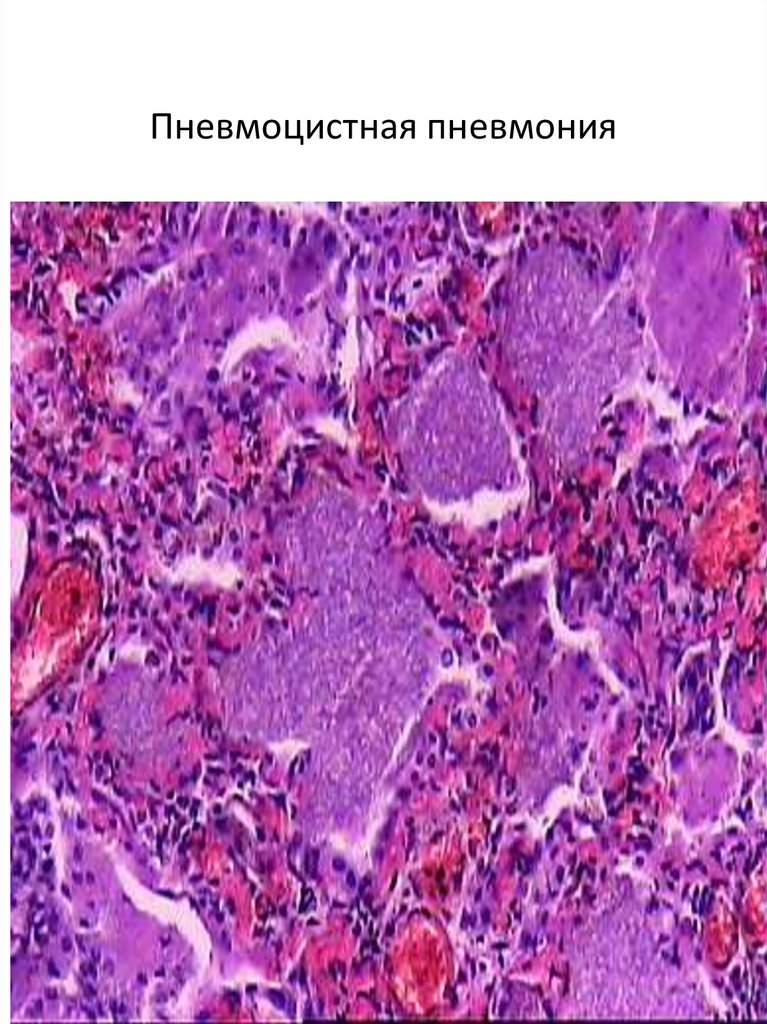

Пневмоцистная пневмония